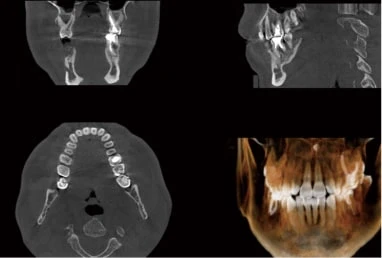

• 歯科用CT

インプラント治療では、顎の骨の「質」と「量」を正確に把握することが重要です。歯科用CTは顎の構造を立体的に確認でき、神経との距離も細かく測定できます。これにより、手術時のリスクを抑えることができます。

• デジタルシミュレーションソフト

撮影したCTデータを専用ソフトで解析し、手術前にコンピューター上で埋入位置をシミュレーションします。あらかじめ計画を立てることで、手術時間の短縮や術後の腫れ・痛みの軽減につながります。